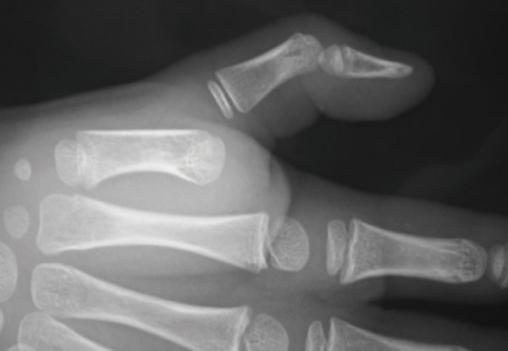

© Frank Fitoussi, La Revue du Praticien Aspect radiographique d'une luxation métacarpo-phalangienne du pouce. Voir : Fitoussi F. Particularités des traumatismes de la main de l'enfant. Rev Prat 2013;63:1253-7.